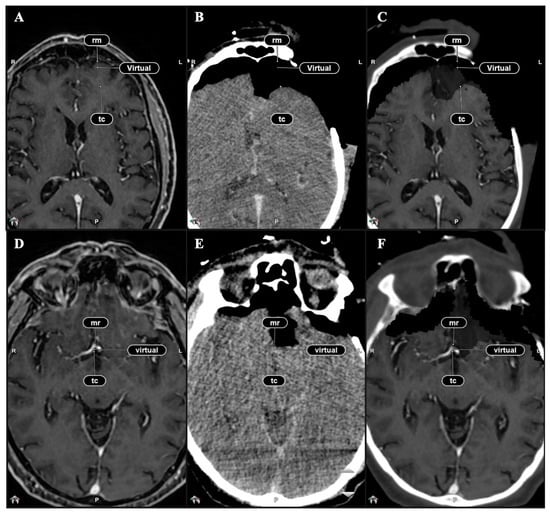

2.5. Qualitative Comparison of iCT, Virtual iMRI, and Post-Operative MRI

3.3. Qualitative Evaluation